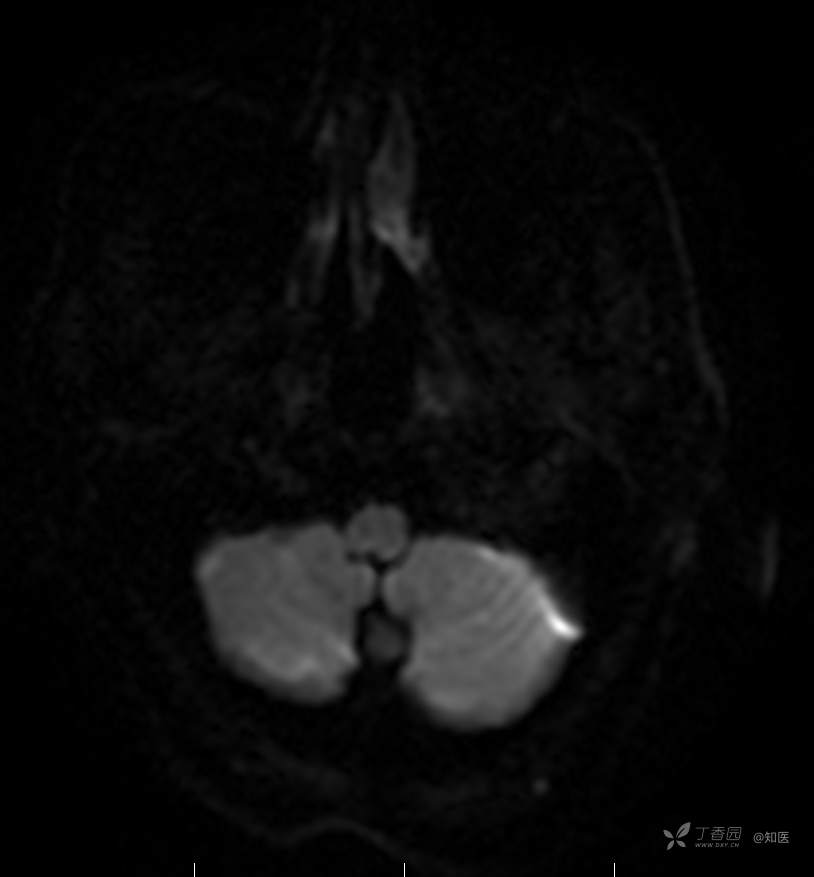

2021-6-15 DWI

2021-06-16日晨查房,患者自觉入院治疗后肢体无力症状较前稍改善,仍有活动后气短,余未诉特殊不适。ALSFRS-R评分:44分(单项均大于等于2分)。血压:123/63mmHg。神经系统查体:GCS 15分,右利手,查体合作,问答切题,粗测智能基本正常。额纹对称,双眼闭目紧,双侧瞳孔等大等圆,直径约3.0mm,对光反射灵敏,眼球运动自如,无眼震,双侧鼻唇沟对称等深,口角无歪斜。悬雍垂居中,双侧软腭抬举良好,咽反射灵敏、转颈、耸肩均一致有力。颈屈肌、颈伸肌力量5级。伸舌居中,无舌肌纤颤及萎缩。双侧岗上肌、岗下肌可见萎缩;双侧三角肌可见偶发肉跳、肌力5级,左侧肱二头肌肌力4+级、右侧4-级,双侧肱三头肌肌力4+级;双手握力可,双手大小鱼际肌及第一骨间肌可见萎缩,左侧明显,左侧手腕背伸力量4级、右侧4+级,双侧拇短展肌肌力4-级,双侧示指伸肌肌力3级,左侧指总伸肌肌力4级、右侧4-级,双侧小指展肌肌力4-级。双上肢肌张力对称减低。左侧肱二头肌反射迟钝、右侧未引出,双侧桡骨膜反射及肱三头肌反射未引出。左侧胸大肌反射阳性、右侧未引出,双侧Rossolimo征阳性、Hoffmann征阴性,下颌反射阴性。腹壁反射未引出。双下肢可见肌肉萎缩,以左侧明显;左侧髂腰肌肌力4级、右侧4-级,双侧股四头肌肌力5级,双足背伸力量3级,左足跖屈力量4级、右足4+级。双下肢肌张力对称基本正常。双侧膝腱反射、跟腱反射迟钝,双侧跖反射消失,双侧巴氏征未引出。右侧大腿外侧肌肉活检瘢痕周围浅感觉缺失,余肢体及躯干深浅感觉正常,共济运动对称正常。颈软,无抵抗,双侧布氏征及克氏征均阴性。辅助检查:微量元素(钙、镁、铁、铜、锌),微量元素测定(铅,镉)[复][2021-6-16 16:11:07]:钙1.19mmol/l;铁9.00mmol/L。急诊电解质七项[复][2021-6-16 10:41:41]:钾3.55mmol/L。血细胞分析+五分类[2021-6-16 9:57:17]:淋巴细胞百分比19.5%。[头颅,扩散成像(DWI)][头颅,磁敏感成像(SWI)][头颅,水抑制成像(FLAIR)][2021-6-16 18:10:50]:1.多发腔梗,脑白质脱髓鞘,脑萎缩。2.DWI:脑实质内未见明显高信号。3.磁敏感成像脑实质内未见明显异常信号灶。MMSE:26分(高中文化水平)。MoCA:23分。ADL评分:14分。ECAS评分:96分(ALS特异67分、ALS非特异29分)。肌电图:提示颈髓、腰髓、胸髓和延髓支配肌肉可见活动期神经源性损害,颈髓和腰髓支配肌肉同时可见慢性期神经源性损害;提示脊髓前角细胞损害可能,请结合临床。心电图大致正常。外送基因检查:TBK1基因杂合子,提示额颞叶痴呆和(或)肌萎缩性侧索硬化症4型。二线主治医师查看患者后示:1.患者基因检查结果显示TBK1基因杂合子,提示额颞叶痴呆和(或)肌萎缩侧索硬化症4型,结合外院影像学检查可见额颞叶萎缩明显,来院后复查头颅FLAIR+DWI+SWI亦提示脑萎缩,量表评估提示认知功能稍减退,ECAS评分基本正常。综上,修正诊断:肌萎缩侧索硬化症(ALS) 额颞叶变性 低钾血症 高血压2级(高危) 多发腔隙性脑梗死。因TBK1基因引起的额颞叶痴呆和(或)肌萎缩侧索硬化症为常染色体显性遗传,患者父亲已逝,母亲健在,诉无明显认知功能障碍或肌肉萎缩等表现,建议患者母亲抽血送检,进一步明确致病基因来源,必要时患者子女也可行基因检查进一步明确。2.患者目前诊断基本明确,根据文献报道,合并FTD的ALS患者整体生存周期较短(约19个月),目前患者发病已1年余,应充分与患者家属沟通病情,告知疾病预后及生存周期情况,同时建议开始口服利鲁唑片,延缓疾病进展。余治疗方案暂不予调整。密观病情变化,遵嘱执行。

2021-06-18出院总结: 卫某某,男,60岁,以“四肢僵硬1年,加重伴无力半年”之主诉入院。查体:生命体征平稳,心肺腹查体无明显异常。神经系统查体:GCS 15分,右利手,查体合作,问答切题,粗测智能基本正常。额纹对称,双眼闭目紧,双侧瞳孔等大等圆,直径约3.0mm,对光反射灵敏,眼球运动自如,无眼震,双侧鼻唇沟对称等深,口角无歪斜。悬雍垂居中,双侧软腭抬举良好,咽反射灵敏、转颈、耸肩均一致有力。颈屈肌、颈伸肌力量5级。伸舌居中,无舌肌纤颤及萎缩。左侧肱二头肌肌力4+级、右侧肱二头肌及双侧三角肌肱三头肌肌力5级;左手大小鱼际肌可见萎缩,左手握2指松、右手握力可,左手拇短展肌、示指伸肌、指总伸肌及抬腕力量3级,右手拇短展肌、示指伸肌、指总伸肌及抬腕力量4-级。双上肢肱二头肌反射、肱三头肌反射、桡骨膜反射均对称减低;双侧Hoffmann征、Rossolimo征、胸大肌反射及掌颏反射阴性,下颌反射阴性。双侧上、中、下腹壁反射可引出。左侧髂腰肌肌力4-级、右侧髂腰肌肌力4级,双侧股四头肌肌力5-级;右足背伸力量3级、左足背伸力量2级,双足跖屈力量5级。双下肢膝腱反射、跟腱反射对称减低;双侧膝阵挛、踝阵挛未引出。双侧巴氏征、Chaddock征均未引出。右侧大腿外侧肌肉活检处周围浅感觉减退,余四肢及躯干部深浅感觉正常,共济运动对称正常。颈软,无抵抗,双侧布氏征及克氏征均阴性。辅助检查:肌电图(2021-05-08,某军医大学附属医院):神经源性损害(颈段、腰骶段受累,胸段可疑;重复神经电刺激(低频、高频)可见左腋神经递减现象。 肌肉活检(2021-05-18,某军医大学附属医院):(右股四头肌)考虑神经源性损害,建议结合临床除外运动神经元病等。入院诊断:1.肢体无力:肌萎缩侧索硬化症(ALS);2.高血压1级(中危)。入院后查血清蛋白电泳:α2-球蛋白6.50%。凝血六项:血浆凝血酶原时间比值0.93;凝血酶原国际标准化比值0.93。贫血因子三项:维生素B12>1476.00pmol/L。平诊肝功十三项+平诊心肌酶谱五项+血同型半胱氨酸测定+平诊血脂八项+平诊肾功七项+平诊电解质八项:尿素3.05mmol/L;肌酐49umol/L;钾3.15mmol/L;高密度脂蛋白0.99mmol/L;载脂蛋白A1.131g/L;脂蛋白(a)333mg/L;肌酸激酶420U/L;总胆红素22.1umol/L;直接胆红素5.4umol/L。微量元素(钙、镁、铁、铜、锌),微量元素测定(铅,镉):钙1.19mmol/l;铁9.00mmol/L。急诊电解质七项:钾3.55mmol/L。血细胞分析+五分类:淋巴细胞百分比19.5%。[头颅,扩散成像(DWI)][头颅,磁敏感成像(SWI)][头颅,水抑制成像(FLAIR)]:1.多发腔梗,脑白质脱髓鞘,脑萎缩。2.DWI:脑实质内未见明显高信号。3.磁敏感成像脑实质内未见明显异常信号灶。MMSE:26分(高中文化水平)。MoCA:23分。ADL评分:14分。肌电图:提示颈髓、腰髓、胸髓和延髓支配肌肉可见活动期神经源性损害,颈髓和腰髓支配肌肉同时可见慢性期神经源性损害;提示脊髓前角细胞损害可能。血尿粪常规、免疫八项、风湿三项、血沉、传染指标、血同型半胱氨酸、糖化血红蛋白等未见明显异常。心电图、肺通气功能大致正常。住院期间给予营养神经、清除氧自由基等对症支持治疗。现患者诊断基本明确,生命体征平稳,一般情况良好,可予今日出院。出院诊断:1.肌萎缩侧索硬化症(ALS);2.额颞叶变性;3.低钾血症;4.高血压2级(高危);5.多发腔隙性脑梗死。出院医嘱:1.注意休息,加强营养,低盐、高蛋白高纤维素饮食,注意休息,适当锻炼,避免剧烈运动及重体力劳动。2.出院继续口服药物:甲钴胺 500ug/次,3次/日;辅酶Q10 10mg/次,3次/日;维生素E 100mg/次,2次/日;美金刚 10mg/次,1次/日;利鲁唑片,50mg/次,2次/日,与餐间隔1.5-2小时。3.出院继续用依达拉奉(必存)60mg+0.9%氯化钠 200ml,静滴,1次/日(首疗程14天,后每疗程10天,间隔20天,共使用6个疗程)。4.1月后门诊复查血常规、肝肾功能、电解质功能;3月后我科门诊再次复诊。5.不适随诊。